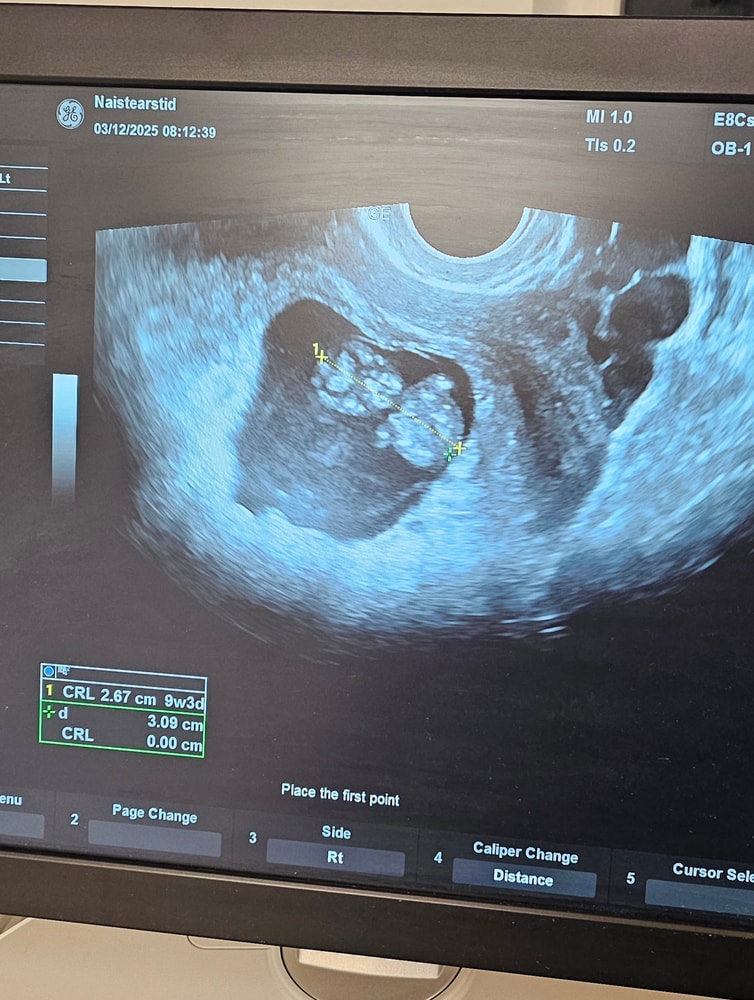

Узи 6 Нед 6 дней

Обследования, узи, анализыКтр 7 мм

плодное яйцо 21 мм

желточный мешочек 4 мм

по размерам отстаем на два денечка, в целом не страшно сказали) главное сердцебиение +